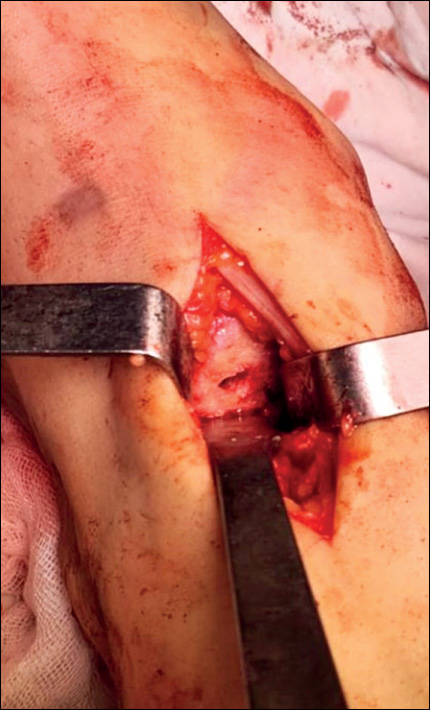

В ходе операции применялась спинальная анестезия. Положение на операционном столе — на спине. Тыльным доступом между сухожилиями передней большеберцовой мышцы и длинным разгибателем первого пальца была выполнена артротомия таранно-ладьевидного сустава. Произведено удаление костно-хрящевых экзостозов по тыльной поверхности головки таранной и ладьевидной кости. По направителю выполнена резекция поражённой суставной поверхности головки таранной кости (рис. 5).

Рис. 5. Резецированный фрагмент головки таранной кости.

Fig. 5. Resected fragment of the head of the talus.

Наружно-боковым доступом был выделен передний суставной отросток пяточной кости и произведена его остеотомия. Это позволило мобилизовать и вывести в рану культю головки и шейки таранной кости без дополнительного рассечения связочного аппарата стопы. У данного пациента в головке таранной кости была обнаружена и интраоперационно выделена киста. Была выполнена её экскохлеация до кровоточащей костной ткани (рис. 6).

Рис. 6. Киста головки таранной кости.

Fig. 6. Cyst of the head of the talus.

Дефект головки таранной кости заполнен костными губчатыми аллотрансплантатами. По анатомической оси шейки таранной кости проведена спица-направитель. По спице при помощи канюлированного рашпиля был сформирован канал для ножки эндопротеза. Рашпиль и спица удалены. В сформированный канал в шейке таранной кости установлен керамический эндопротез головки таранной кости (рис. 7).

Рис. 7. Интраоперационный вид правой стопы после имплантации эндопротеза головки таранной кости.

Fig. 7. Intraoperative view of the right foot after implantation of the endoprosthesis of the head of the talus.